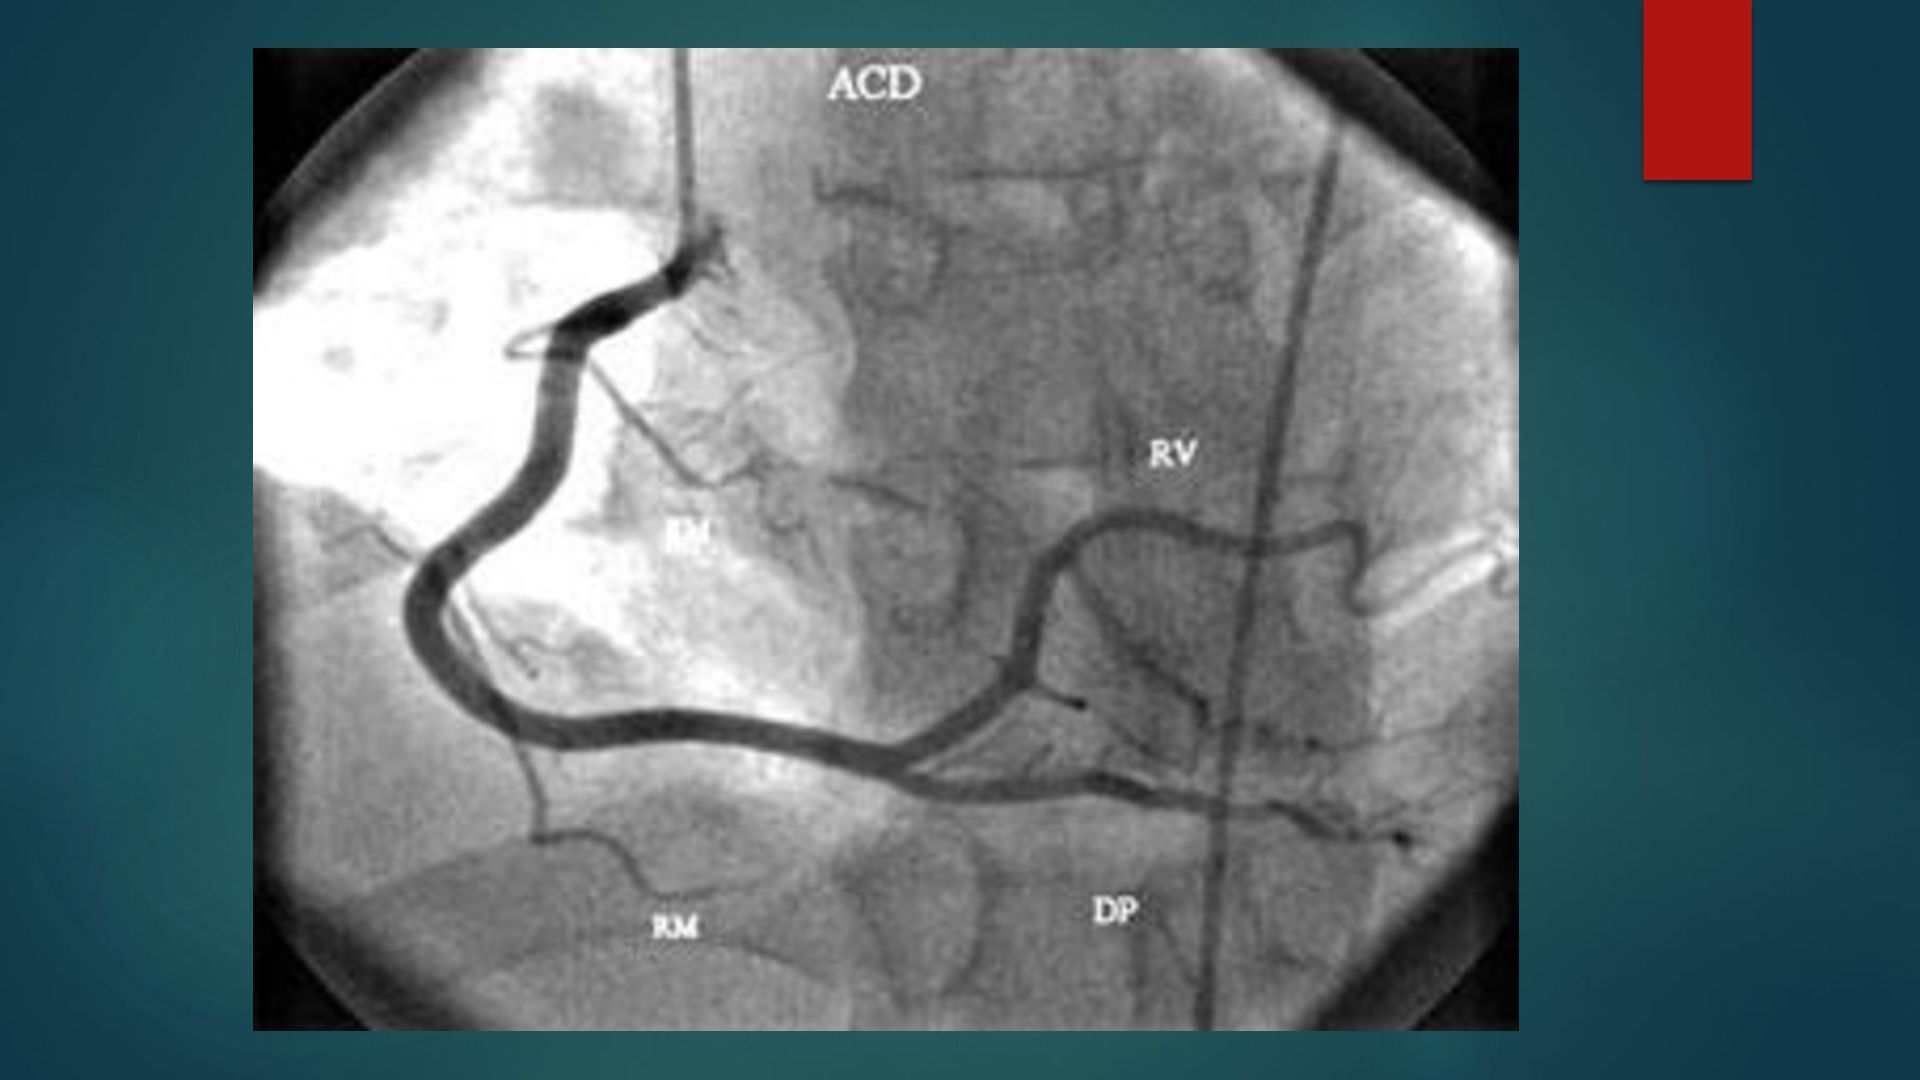

o g a c a r d i o v a s c u l a r ANATOMÍA Y FISIOLOGÍA CARDIOVASCULAR D r a . I s a m a r G . C h a v a r r i a B e r n a r d i n o